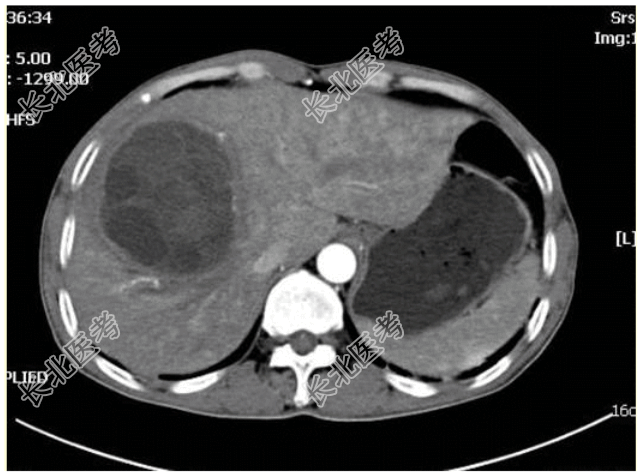

- [材料题] 患者男,52岁,因“反复中上腹胀痛伴畏寒、低热1个月余,加重5 d”来诊。腹部CT:右肝囊性占位,如图所示。